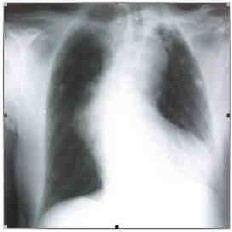

Colega quer transferir às 3 horas da manhã, do hospital de Viamão, paciente com 72 anos atendido na Emergência, apresentando dor retroesternal há duas horas. Relata que o paciente está com PA 110/70mmHg e sudorético. A ausculta cardíaca na fúrcula esternal (Fig. A), o Rx de tórax (Fig. B) e o eletrocardiograma (Fig. C), transmitidos via eletrônica, estão representados abaixo.

Fig. B